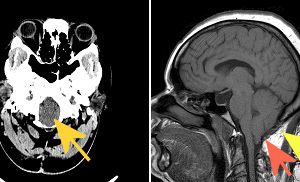

Wilson’s Disease

Wilson disease is an autosomal recessive disorder of copper metabolism. Patients with the disease experience excessive deposition of copper in the liver, brain, and other tissues. It appears that the primary defect... Read more »